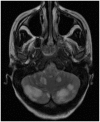

Results: Eight out of the 20 patients included in the study were on cyclosporine or tacrolimus based immunosuppressant therapy for kidney transplant. Four patients had severe hypertension at presentation. The most common MRI finding was high T2-fluid-attenuated inversion recovery (FLAIR) signal in the cortex and subcortical white matter of both cerebral hemispheres, particularly in the parietal and occipital lobes (n=16). The second most common MRI finding was increased leptomeningeal FLAIR signal (n=7). Out of seven patients with leptomeningeal signal, five demonstrated leptomeningeal enhancement as well. Four out of these seven patients had no other parenchymal findings.

Conclusion: Childhood PRES is commonly seen in the setting of immunosuppressant therapy for kidney transplant, severe hypertension and cancer treatment. There was high incidence of increased leptomeningeal FLAIR signal and leptomeningeal enhancement in our study. It supports the current theory of endothelial injury with increased microvascular permeability as the potential pathophysiology of PRES. Also, absence of elevated blood pressure in majority of the patients in our study supports the theory of direct endothelial injury by some agents leading to vasogenic edema.